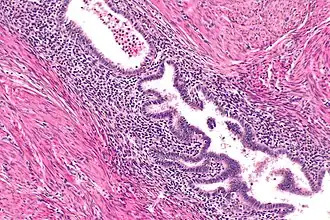

High magnification micrograph of uterine adenomyoma.

Uterine adenomyoma is the focal form of uterine adenomyosis. Adenomyosis most commonly presents with numerous small collections of endometrial glands and stroma spread diffusely throughout the myometrium, intermixed with the myometrial smooth muscle. In contrast, a uterine adenomyoma is an isolated nodular mass of endometrial tissue with surrounding smooth muscle, either embedded within the myometrium or extending from the endometrium into the uterine cavity in the form of a polyp.[2]